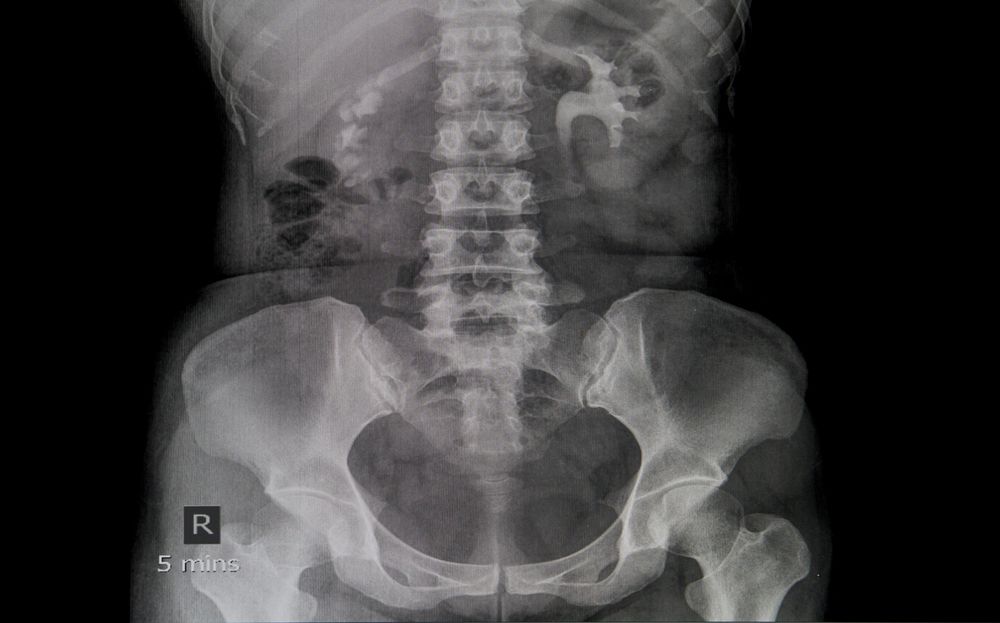

Vyšetření IVU probíhá podobně jako klasické rentgenové vyšetření s tím, že pacientovi je do žíly podána kontrastní látka, která se vstřebá do krve. Ledviny poté tuto látku filtrují a vylučují do moči, jíž je odváděna z těla ven. Vyšetřovaný během zákroku leží a jsou prováděny série rentgenových snímků, které jsou díky kontrastu velmi přehledné. Lékař tak sleduje velikost a funkci ledvin i to, jak kontrastní látka prochází močovými cestami.